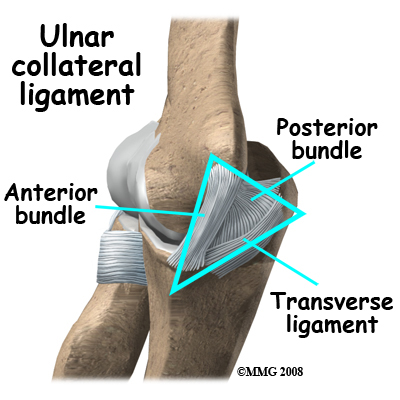

In the elbow, two of the most important ligaments are the ulnar collateral ligament (UCL) and the lateral collateral ligament. The UCL is also known as the medial collateral ligament. The ulnar collateral ligament is on the medial (the side of the elbow that\'s next to the body) side of the elbow, and the lateral collateral is on the outside. The ulnar collateral ligament is a thick band of ligamentous tissue that forms a triangular shape along the medial elbow. It has an anterior bundle, posterior bundle, and a thinner, transverse ligament.

Together these two ligaments, the ulnar (or medial) collateral and the lateral collateral, connect the humerus to the ulna and keep it tightly in place as it slides through the groove at the end of the humerus. These ligaments are the main source of stability for the elbow. They can be torn when there is an injury or dislocation of the elbow. If they do not heal correctly the elbow can be too loose or unstable. The ulnar collateral ligament can also be damaged by overuse and repetitive stress, such as the throwing motion.